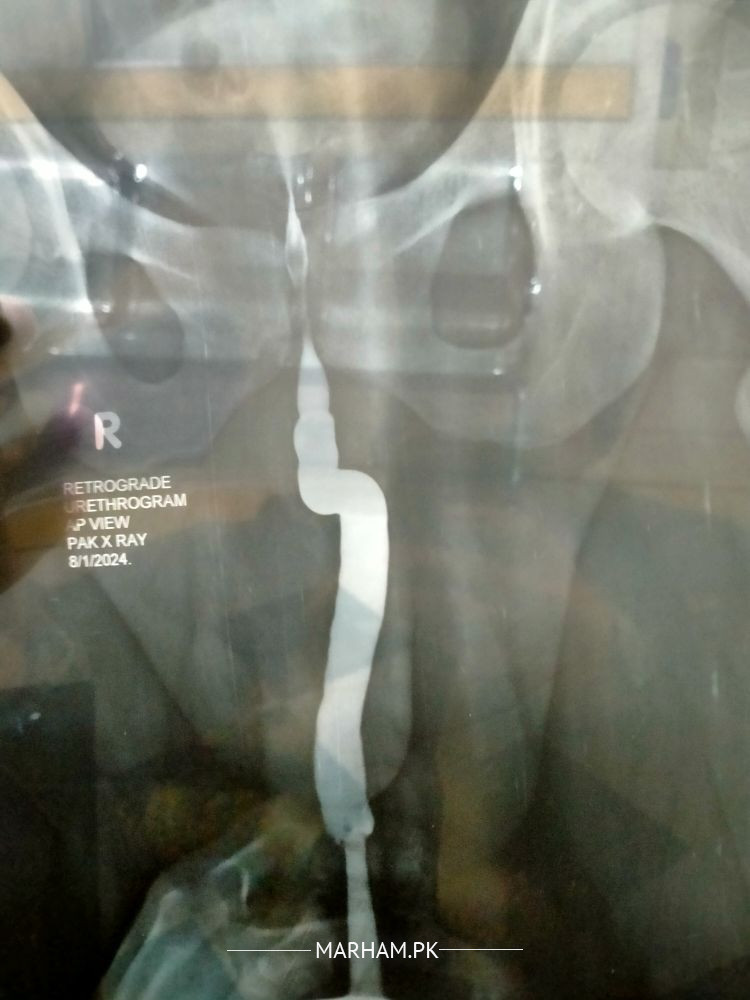

Asking For Self, Male 22, GUJRANWALA

sir is ma doctor na Stricture confirmed Kiya hai Ka ni please tell but nelton 16 fr pass easily

Poorly performed urethrogram.likely stricture but need to repeat urethrogram. I do my own urethrogram for my patients to treat them

stricture h apki report k according

i mark the strictural area most probably

urethral stricture is confirmed in report .for proper treatment get ur appointment with in few days it will be treated

no stricture.. just normal RUG